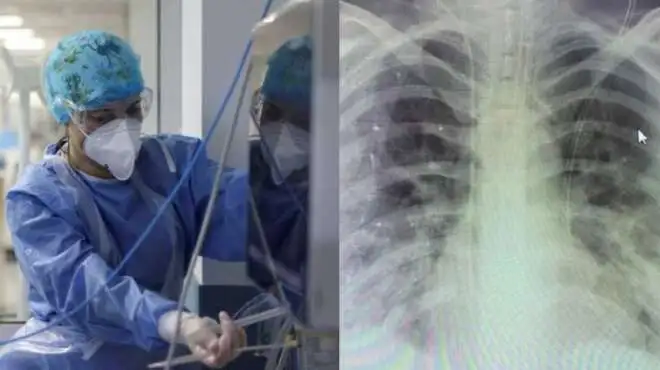

41χρονη ανεμβολίαστη: Η ακτινογραφία θώρακα και τα λόγια του γιατρού

Ο Κοσμάς Σαραφίδης ανέβασε φωτογραφία στην προσωπική του σελίδα με την ακτινογραφία θώρακα της γυναίκας, αναφέροντας:

«Ακτινογραφία θώρακα ανεμβολίαστης εγκύου που διασωληνώθηκε χτες και γέννησε πολύ πρόωρα λόγω της βαρύτητας της κατάστασης της. Μόνο ο μισός από τον κάθε πνεύμονα της λειτουργεί. Άγνωστη η πρόγνωση της μητέρας. Και ένα νεογνό που θα μπορούσε να γεννηθεί στην ώρα του, τελειόμηνο, και να αποφύγει όλους τους κινδύνους της προωρότητας. Αυτό που γράφεται σε ανάλογες περιπτώσεις, ότι δηλαδή το μωρό σώθηκε, είναι τελείως ανακριβές. Μήνες εντατικής νοσηλείας για να επιβιώσει και μόνο! Και με νευροεξέλιξη απρόβλεπτη σε μεγάλο βαθμό! ΚΡΙΜΑ, ΚΡΙΜΑ! Τα σχόλια είναι περιττά!».